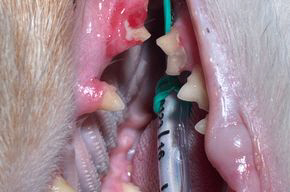

Dabei kommt es durch Aktivität von Odontoklasten („Zahnabbauzellen“) zu einem fortschreitenden Abbau der Zahnhartsubstanz (Zement, Dentin und teils Schmelz) teils bis in die Pulpa (Wurzelkanal) ziehend. Betroffene Zähne sind oft sehr schmerzhaft, auch wenn äußerlich zunächst wenig zu erkennen ist.

- Beginn meist am Zahnhals unterhalb des Zahnfleischrandes